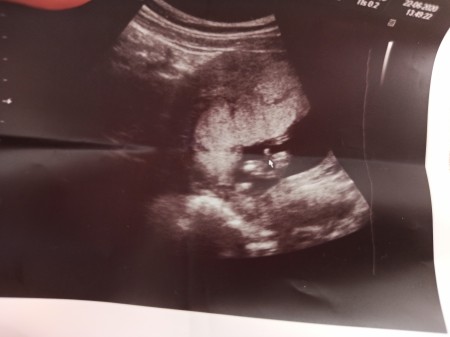

imageKızlar 14. Haftamda doktora gittim %100 erkek dedi buda bacak arasının fotosu acaba sonradan cinsiyet değişir mi yanılma payı aranızda erkek bebeği olanlar tecrübeli anneler bakabilir mi?

Gebelik haftası 14+5